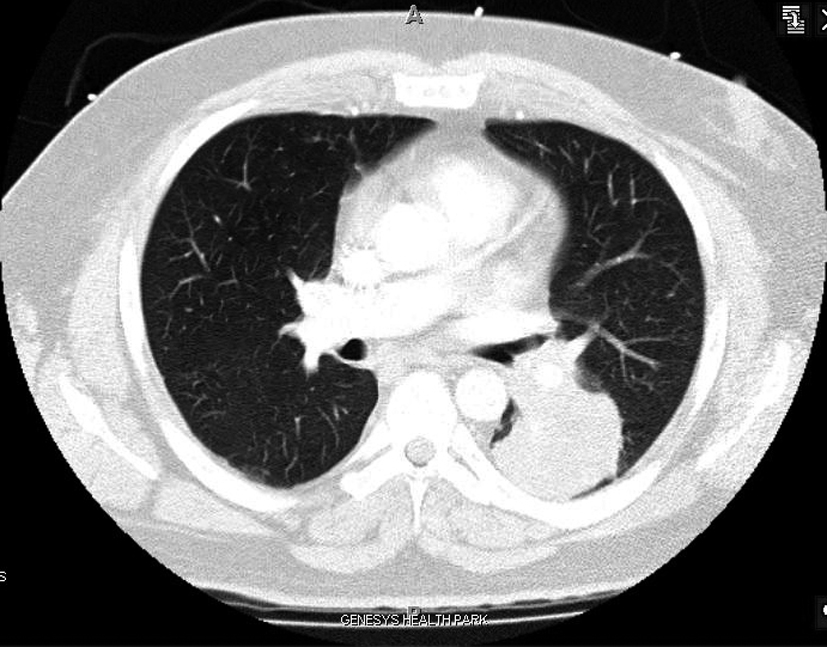

A 42 year old Caucasian male with no history of smoking and with a past medical history significant for hypertension and hypercholesterolemia presented to the emergency department (ED) with complaints of worsening shortness of breath over the past month. Upon further examination the patient complained of a 2 - 3 month history of bilateral upper and lower extremity pain, a 50 pound weight loss over 5 months, night sweats and persistent fever and chills. A computed tomography angiogram was ordered in the ED due to the suspicion of pulmonary embolism which was subsequently negative for pulmonary embolism (PE), but a 5.5 x 5.0 cm mass was noted in the left lower lobe that encased the bronchus and pulmonary artery (Fig. 1). Computed tomography (CT) guided biopsy was performed and the subsequent pathology report described findings consistent with sarcomatoid carcinoma. While awaiting pathology of the lung mass, further examination into the extremity pain was worked up and a bone scan was performed (Fig. 2) On bone scintigraphy there is increased peripheral periosteal and cortical uptake of technetium-99m MDP bilaterally in the femurs, tibias, clavicles and midfeet demonstrating the unique characteristics that are consistent with hypertrophic pulmonary osteoarthropathy secondary to the lung cancer. The patient underwent a pneumonectomy via muscle sparing thoracotomy and after recovering from ventilator dependent respiratory failure, secondary to acute respiratory distress syndrome, the patient began to demonstrate improvement in his symptoms. The pain in his legs started to subside and the patient is schedule to follow up in the clinic to begin chemotherapy.

![]() Click for large image | Figure 1. Sarcomatoid Carcinoma located in LLL on CT Angio. |